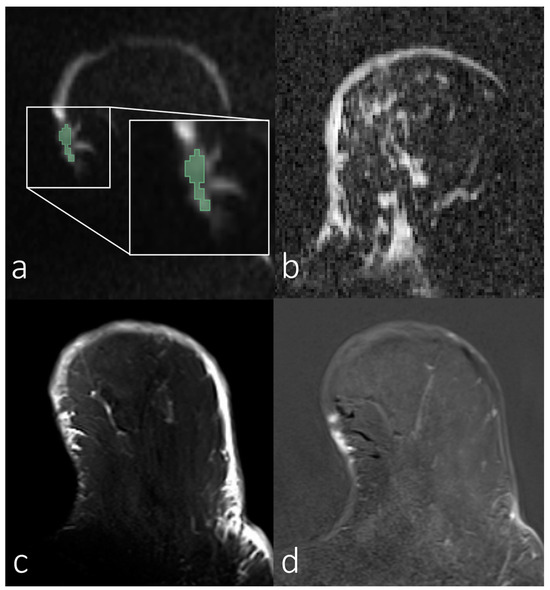

3.2. Analyses of First-Order Statistics Using the ADC

3.3. Evaluation of SNR in the Skin for Assessing ADCs in Skin Pathologies